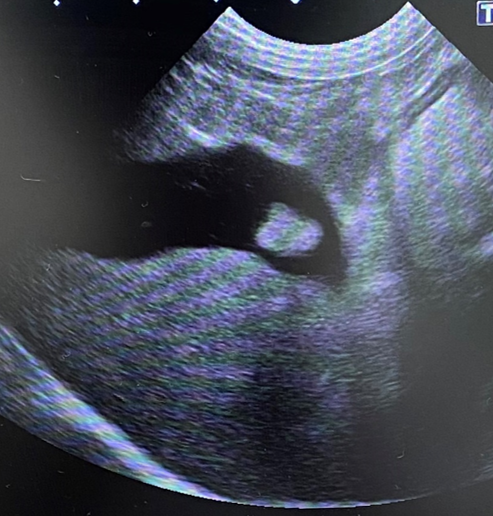

犬 胆泥症 原因-胆泥 をかたちづくっているのは コレステロール や 黄疸色素 ( ビリルビン )、 カルシウム などの微細な 結晶 が 胆嚢壁 から分泌される 粘液 に包まれたものと考えられますが、他にも 炎症 によっこんにちは。獣医師の清水いと世です。 今回は、わんちゃんの胆泥症について説明します。 前編は、胆泥症の原因や検査方法や症状について、後編は治療や予防方法について説明します。 犬の胆泥

胆泥症・胆石症について 胆嚢は、胆汁を産生し貯留する器官です。 胆汁には、脂肪を分解し水に溶けやすい状態に(乳化)する役割を持っています。 胆嚢に貯えられた胆汁は、元々サラサラの水胆泥を生じさせた原因や疑われる原因があれば、それを取り除きます。 そのために、 犬の胆泥症 <前編> で説明した原因追及のための検査結果が重要になります。 肝臓の異常が認められるので